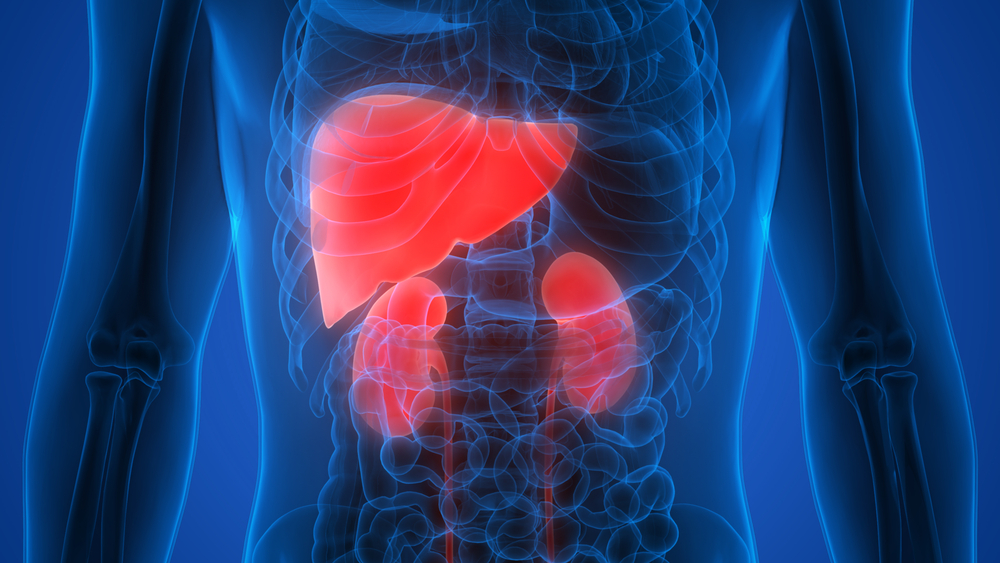

Анатомия желудка и сердца: визуализация и изучение

Раздел: Фотопанорама